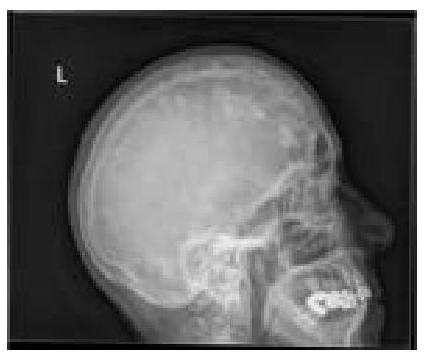

What type of lesions in the skull calvarium can be identified on this X-ray?

Explanation: ***Brain metastases (Skull metastases)*** - The image shows multiple **lytic lesions** in the skull calvarium, which are characteristic of metastatic disease that has spread to bone - Metastases from primary cancers (lung, breast, kidney, thyroid, prostate) commonly involve the skull and appear as **punched-out or moth-eaten lytic lesions** - While plain X-rays cannot visualize brain parenchyma, they can detect **bony destruction** caused by metastatic deposits in the skull - These appear as well-defined osteolytic lesions without sclerotic margins *Multiple myeloma* - Multiple myeloma typically presents with **multiple punched-out lytic lesions** in the skull that can appear very similar to metastases - However, multiple myeloma is a **primary bone marrow malignancy** rather than metastatic disease - Key differentiator: myeloma lesions are usually more uniform in size and distribution - Clinical context (monoclonal protein, anemia, renal dysfunction) helps distinguish from metastases *Osteosarcoma* - Osteosarcoma is a **primary bone tumor** that usually causes a mixture of lytic and blastic (bone-forming) lesions - Typically presents with **sunburst or spiculated periosteal reaction** and soft tissue mass - Usually occurs as a **solitary aggressive lesion** in younger patients, not multiple scattered lesions - Rarely occurs in the skull compared to long bones *Osteomyelitis* - Osteomyelitis is an **infection of the bone** that causes bone destruction and reactive new bone formation - Shows features of **bone destruction, periosteal reaction**, and possibly sequestra (dead bone fragments) - Typically presents as a **focal process** with surrounding inflammatory changes - Does not produce the multiple discrete lytic lesions pattern seen in metastatic disease